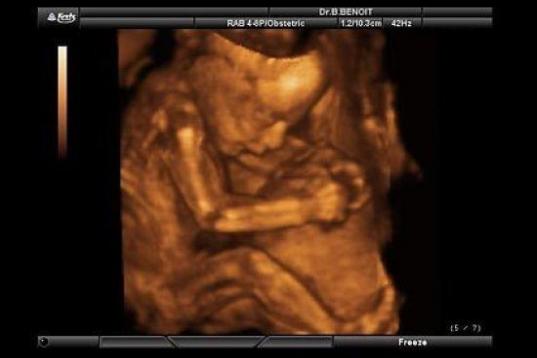

En esta galería puedes ver en fotos como es el desarrollo de un feto de semana en semana:

Desarrollo del feto, en fotos